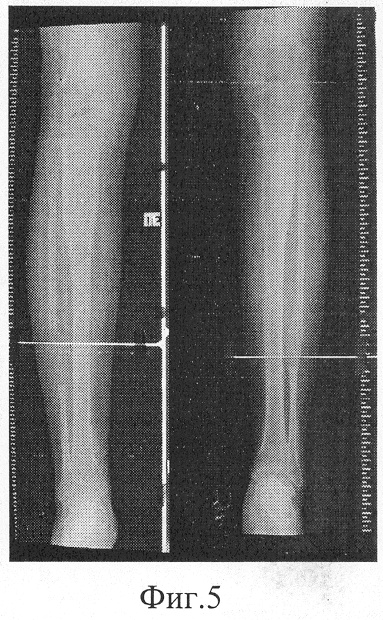

фиг.5 – фоторентгенограмма голеней больного после окончания лечения (на момент демонтажа аппарата).

В результате лечения, общая продолжительность которого составила 181 день, достигнуто увеличение продольных размеров обеих голеней на 7,8 см. На момент демонтажа аппарата: ось сегмента правильная, движения в коленном и голеностопном суставах в пределах нормы, больной ходит с полной нагрузкой на оперированную конечность.